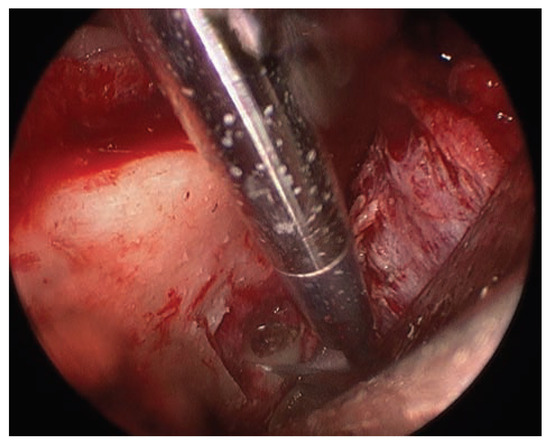

Report of a Case

![]() |